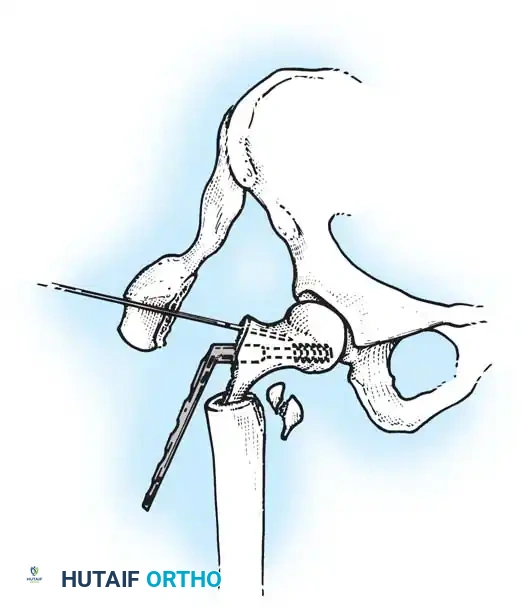

The patient is placed supine on a radiolucent fracture table. The operative leg is secured in a traction boot, and the well leg is placed in a hemilithotomy position or scissored posteriorly to allow unobstructed access for the C-arm fluoroscope.

Proper patient positioning on the fracture table is paramount. Ensure the C-arm can freely rotate from AP to lateral without obstruction.

2. Surgical Approach (Lateral)

A longitudinal incision is made over the lateral aspect of the proximal femur, starting at the tip of the greater trochanter and extending distally. The fascia lata is incised, and the vastus lateralis is elevated or split to expose the lateral femoral cortex.